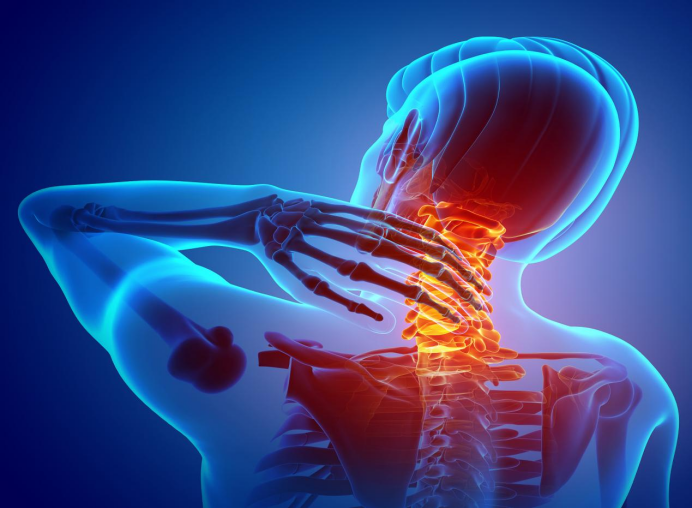

軟骨素(CS)是一種胺聚糖類大分子酸性多糖,采用分離的方法在動物軟骨中提取高分子量酸性茹多糖,屬于糖胺聚糖 (Glycosaminoglycan, GAG)類,是細胞外基質(extracellular matrix, ECM)的主要組分。其作用是促進軟骨再生,并且具有抗炎、降血脂、預防關節炎等效果。

早年研究中,CS 通過細胞表面受體介導,降低 p38絲裂原活化蛋白激酶和信號調節激酶 1/2的磷酸化,從而抑制 NF-κB 的核易位,減少促炎細胞因子如 TNF-α、IL-6 以及促炎酶如磷脂酶 A2、環氧合酶 2、基質金屬蛋白酶-13 和一氧化氮合酶 2 釋放的抗炎途徑在軟骨細胞中得到證明[3] [4],CS 還可能通過該途徑增加骨保護素的表達,抑制破骨細胞的激活[5]。Calamia 等[6]從人類關節軟骨細胞分泌組中鑒定出 18 種可被 CS 調節的蛋白質,并且用 IL-1b 刺激正常軟骨細胞后觀察到 CS 通過減少幾種補體成分(CFAb,C1S,CO3 和 C1R)直接降低炎癥反應,并且發現 CS 以濃度依賴的方式促進血管生成抑制劑血小板反應蛋白-1 的增加,可能是 CS 在骨關節炎(osteoarthritis, OA)中抗新生血管生成的潛在機制。

Korotkyi 等[7]發現 CS 可使大鼠膝關節軟骨中 OA 誘導的前列腺素過氧化物酶 2 和轉化生長因子-β表達上調被抑制。表明 CS 作為藥物可能有助于控制炎性應激的關節分解代謝作用,可用于預防關節退行性變。這些研究解釋了 CS 減輕 OA 癥狀,減緩關節損傷的潛在機制。